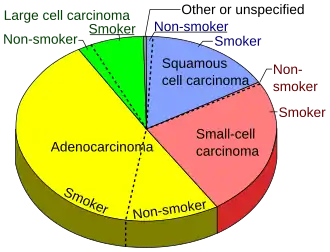

Гистологическая классификация рака лёгкого

| Гистологический тип | Частота (в %) |

|---|---|

| Немелкоклеточный рак лёгкого | 80.4 |

| Мелкоклеточный рак лёгкого | 16.8 |

| Карциноид[32] | 0.8 |

| Саркома[33] | 0.1 |

| Неуточнённая злокачественная опухоль лёгкого | 1.9 |

Согласно гистологической классификации рак лёгкого подразделяется на следующие виды:

I. Плоскоклеточный (эпидермоидный) рак

II. Мелкоклеточный рак

III. Аденокарцинома

IV. Крупноклеточный рак

V. Смешанный рак

Гистологическая характеристика рака лёгкого достаточно условна, поскольку клиническое течение может сильно различаться даже для опухолей с одинаковой структурой. Медленнее всего растёт дифференцированный плоскоклеточный рак; для недифференцированного рака характерно быстрое течение с обширным метастазированием. Мелкоклеточный рак лёгкого принадлежит к числу самых злокачественных опухолей. Он отличается коротким анамнезом, скрытым и быстрым протеканием, ранним метастазированием, плохим прогнозом.